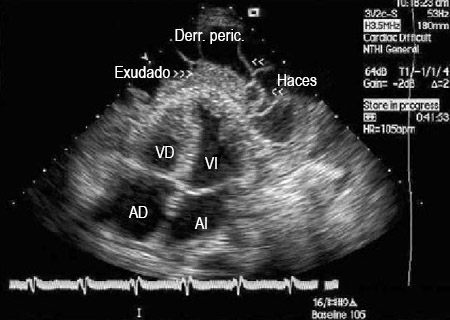

El tamaño del derrame en la ecocardiografía indica el volumen de líquido pericárdico de la siguiente manera:[5]Hoit BD. Pericardial effusion and cardiac tamponade in the new millennium. Curr Cardiol Rep. 2017 Jul;19(7):57.

Trivial (visto solo en sístole)

Reducido (<10 mm), que corresponde a 50-100 mL de líquido pericárdico

Moderado (10-20 mm), que corresponde a 100-500 mL de líquido pericárdico

Grande (>20 mm), que corresponde a >500 mL de líquido pericárdico

Muy grande (>25 mm); normalmente indica >700 mL de líquido pericárdico.